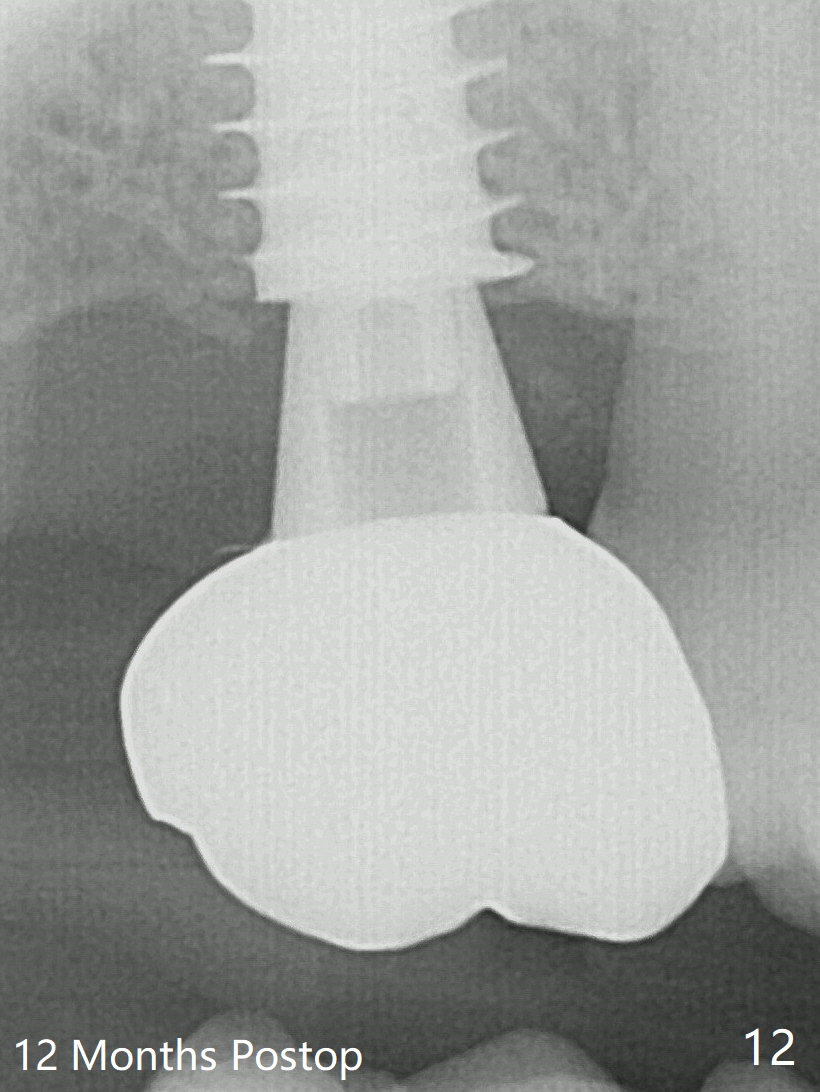

Five months post op, the healing abutment has mobility with light tenderness. The space between the bone and implant is larger than normal (Fig.10). The implant is stable with the healing screw 8 months postop (Fig.11). There is definitive sign of osteointegration 12 months postop (3 months post cementation, Fig.12). The final pair abutment is 5x4(4) mm. The patient is pleased to have the implant for 1 year 7.5 months post cementation (Fig.13).